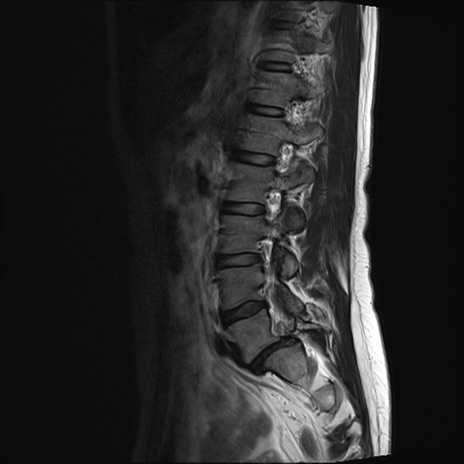

【整形】TIPS症例4 腰椎MRI T2WI(矢状断像)

腰椎MRI

横断像と矢状断像